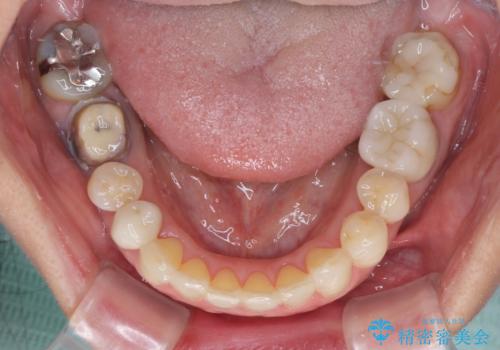

欠損やむし歯の歯をきれいなセラミックに 全顎虫歯治療

- 他院で矯正治療を終えたものの、むし歯や欠損部の治療が進められないとのことで来院された患者様です。

欠損部や、銀歯やむし歯の大きな歯はセラミッククラウンやブリッジに、小さいむし歯はセラミックインレーにて治療を行うこととしました。